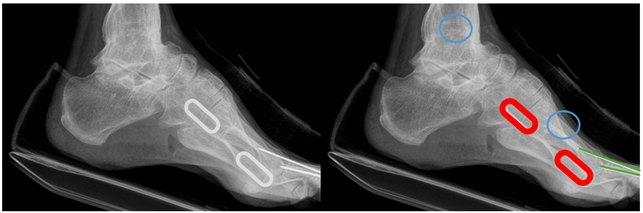

발(Foot): 1st, 2nd metatarsal bone 등 8개 영역의 세그멘테이션과 1번째 발등뼈 관절면 끝을 지정하는 4개의 키포인트, 종자골(sesamoid bone) 영역의 바운딩 박스를 라벨링했습니다.